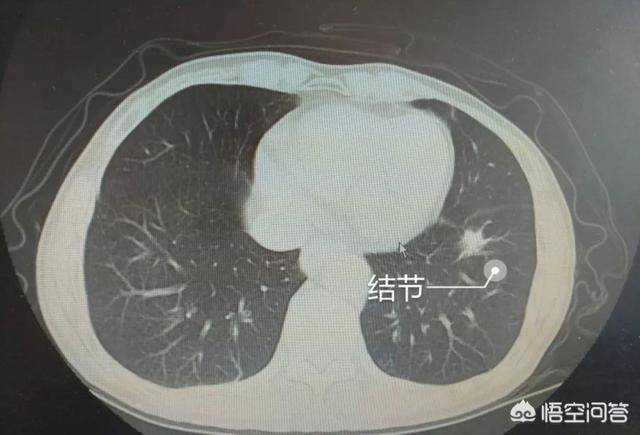

比如这个单发结节,呈混合磨玻璃密度,外侧有胸膜牵拉,内侧有血管进入,考虑肺腺癌。

这样的单发结节也很有潜在危害,及时手术切除,证实为浸润性腺癌。